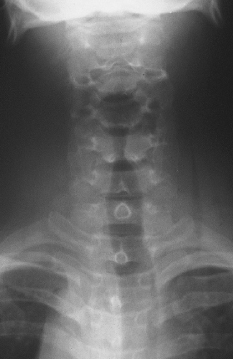

A 32-year-old man was brought to the emergency department after being stabbed in the right side of the neck with a broken piece of glass. The patient immediately underwent carotid angiography; the findings were normal.

Results of an indirect laryngoscopic evaluation and an esophageal examination ruled out injury to the larynx and the esophagus. A roentgenogram of the neck revealed the presence of air in the deep fascial tissue planes of the neck. The patient was otherwise hemodynamically stable.

Air in the neck tissue is a cause of concern, since it may lead to pneumomediastinum. Generally, air in fascial planes of the neck is caused by trauma; the condition also may occur secondary to neck surgery, dental extraction, or deep space infection. The underlying cause needs to be identified and treated.

This patient was observed in the intensive care unit. Within a few days, the air in the neck tissue planes resorbed, and the patient recovered.